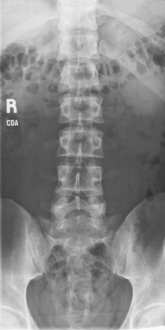

Scoliosis series (Ferguson method) (S)

• 35 × 43 cm L.W. (14 × 17″) or 35 × 92 cm (14 × 36″)

• Compensating filters to produce a more uniform density of spine

Erect, standing or seated, spine aligned and centered to centerline, arms at side, no rotation of pelvis or thorax